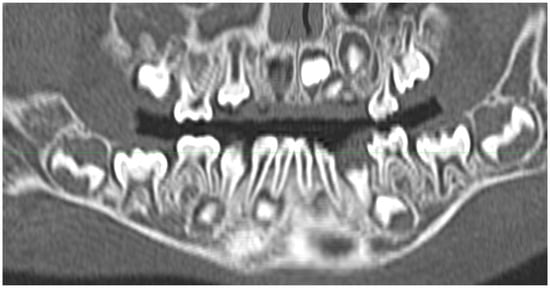

3.1. Anatomy of the Dental Arch

3.1.1. Anatomy of Tooth Structure

3.1.2. Periodontal Tissues

3.2. Dental Development